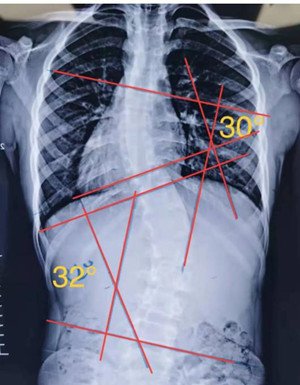

s型侧弯,无论向哪个方向侧躺,对其中一边的弯度都是不利的,这种情况尽量以平躺为主。

针对于腰椎单弯,还有另一种侧躺姿势:比如存在腰椎的左侧弯,凸侧在下

,在顶椎下加一个圆形压垫(将毛巾卷成圆柱体,直径约5-10公分),使其把相反凹侧方向的脊柱给顶起。(顶起后从背后观察,用手去触摸到脊柱在中线上,成为一条直线,说明动作正确。如果顶起程度能达到过矫的效果,为最佳)。